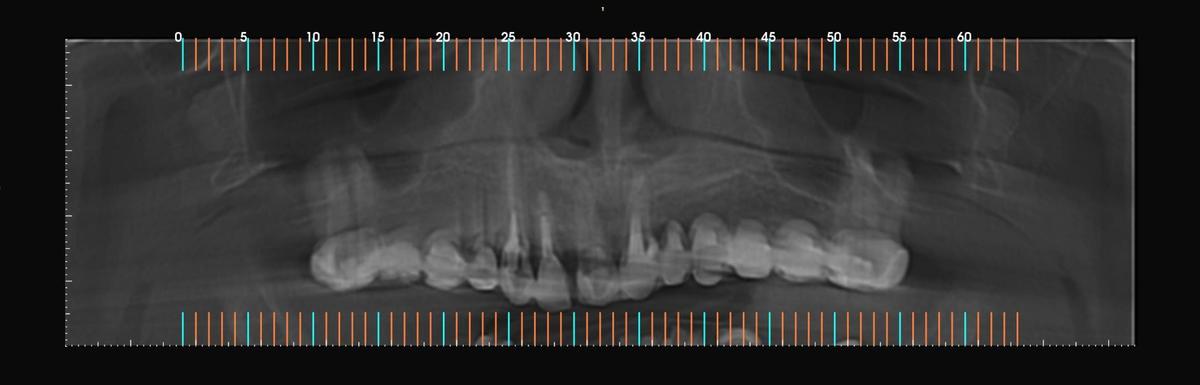

PRÓTESE TOTAL FIXA EM IMPLANTES

M.A.S.L.